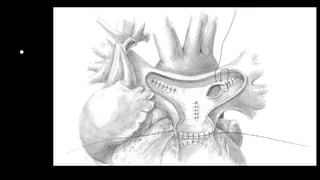

Figure 9 That patch is sutured starting at the edge of

the divided anterior cusp, leaving 1-2 mm protruding

over the free edge of the valve, and

anchoring the patch to the endothelial layers of the

RVOT incision to create a pseudo sinus of Valsalva.

RVOT = right ventricular outflow

trac

Figure 10 Another oval-shaped Cormatrix patch is

sutured from the distal main PA to the RVOT covering

the entire incision. The right atrial

incision is closed after ensuring that there is no

tricuspid regurgitation. The patient is weaned off

bypass per routine protocol. Pacing wires are

placed if any evidence of rhythm problem exists